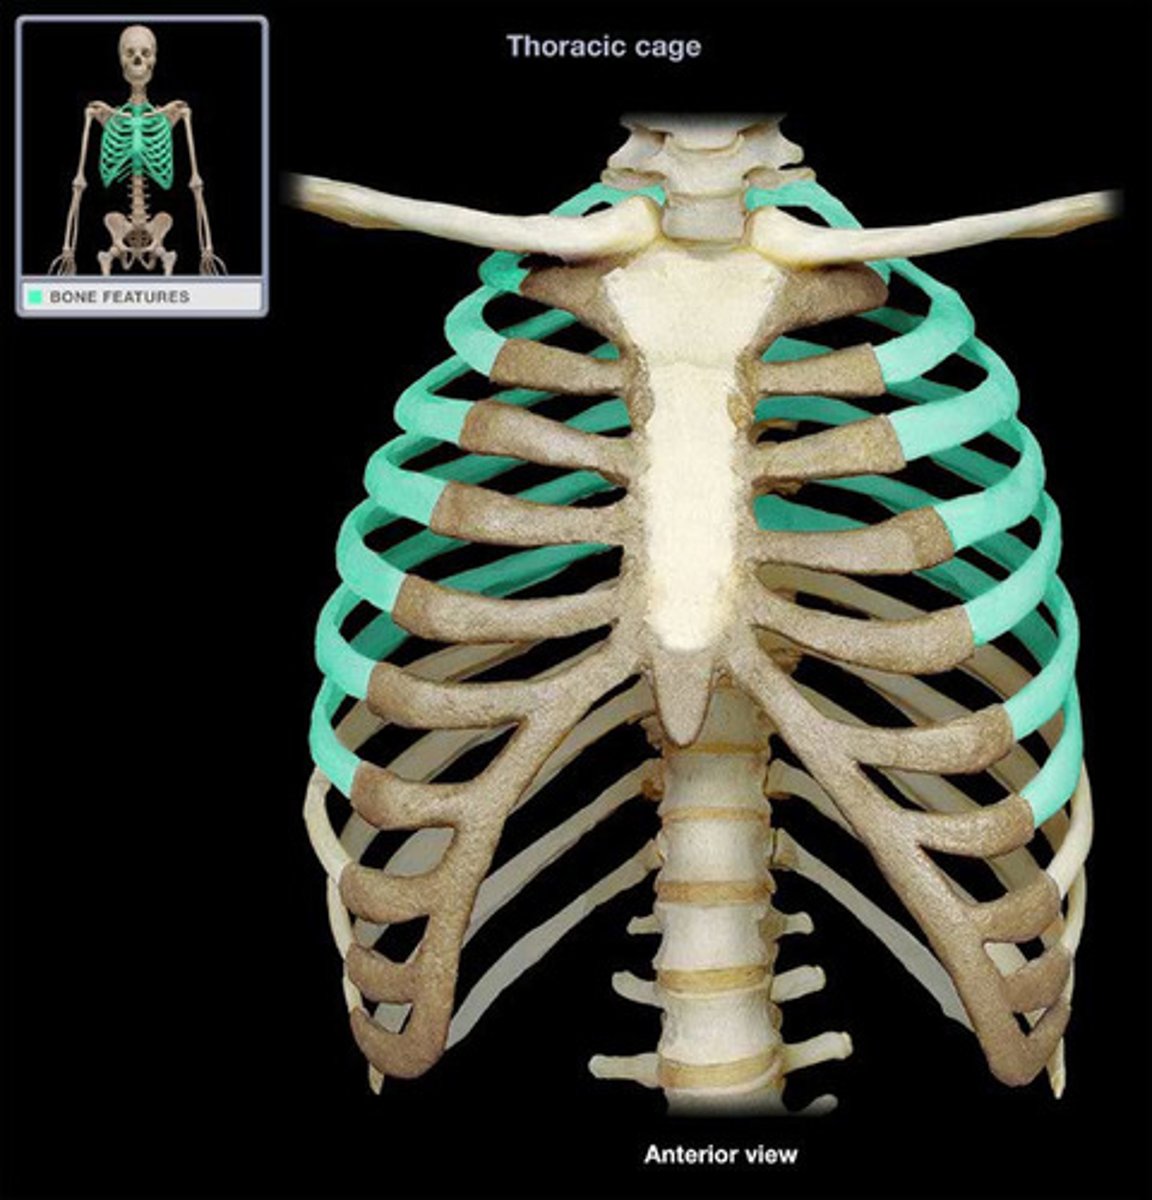

ribs

What is this bone?

true ribs

1-7

false ribs

8-12

floating ribs

11-12

costal cartilages

What is this structure?